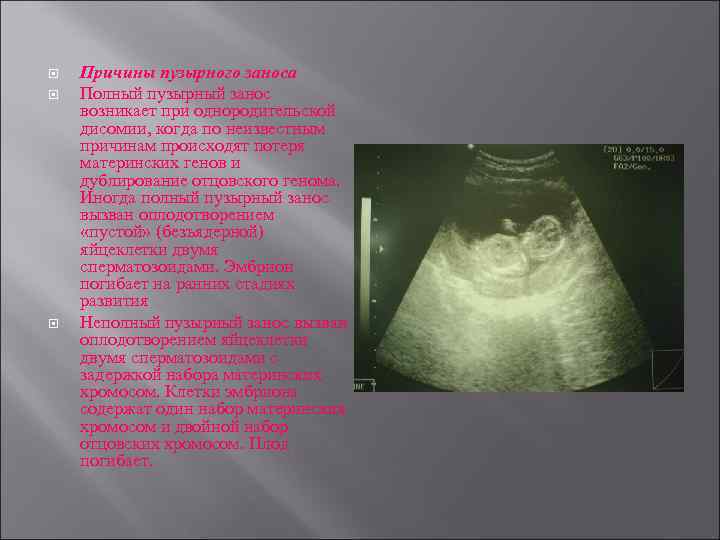

Причины пузырного заноса Полный пузырный занос возникает при однородительской дисомии, когда по неизвестным причинам происходят потеря материнских генов и дублирование отцовского генома. Иногда полный пузырный занос вызван оплодотворением «пустой» (безъядерной) яйцеклетки двумя сперматозоидами. Эмбрион погибает на ранних стадиях развития Неполный пузырный занос вызван оплодотворением яйцеклетки двумя сперматозоидами с задержкой набора материнских хромосом. Клетки эмбриона содержат один набор материнских хромосом и двойной набор отцовских хромосом. Плод погибает.